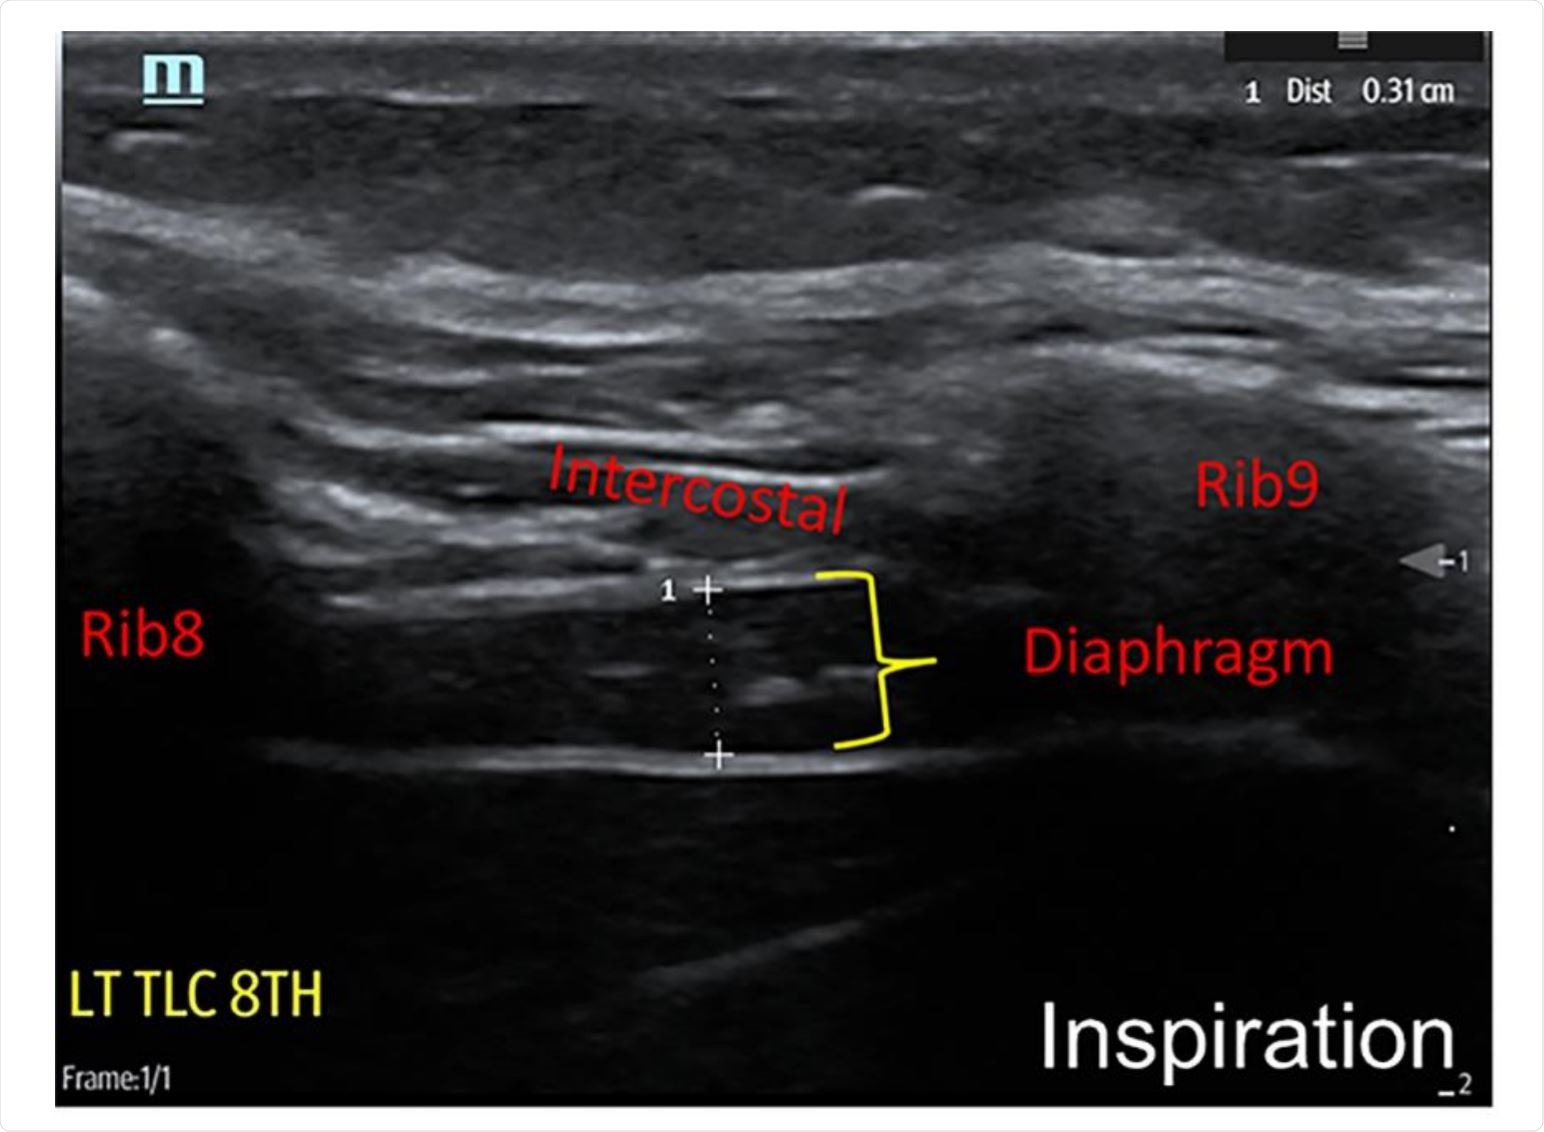

A portable ultrasound system was used to assess the diaphragm muscle; more specifically, individual characteristics were used to guide the selection of either a 6-14 MHz linear array or a 2-5 MHz curvilinear array in order to maximize the image clarity.

In any case, diaphragm thickness was assessed at the maximum inspiration and end of expiration, while the thickening ratio has been calculated as thickness at maximal inspiration divided by thickness at end-expiration.